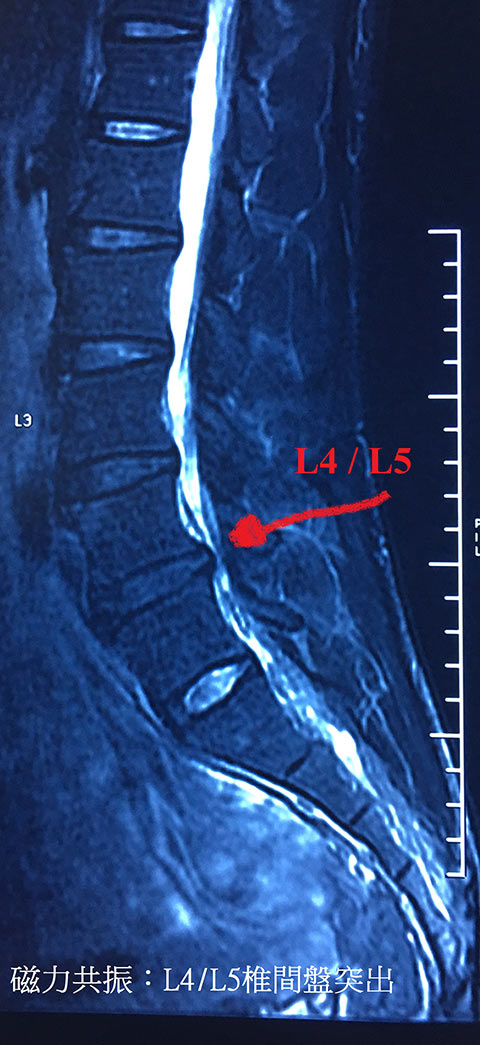

經家庭醫生轉介到骨科醫生接受了磁力共振檢查,報告顯示腰椎L4、L5椎間盤有突出情況,壓著神經線引起痛楚。骨科醫生提議以手術處理,但他卻甚害怕 (純因家族其他成員的經歷) 更不想貿貿然便作該決定。